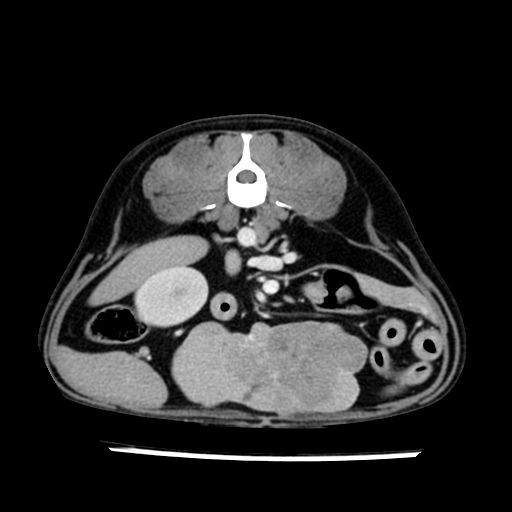

prescritto esame TAC

sequenza immagini limitata al fegato reni e surreni

le immagini ecografiche rispetto alla tac datano circa 7 mesi prima ,le surrenali sono normali nonostante il test acth sia risultato positivo .all’esame TAC dopo diversi mesi risultano aumentate armonicamente nel volume e si individua un forte sospetto di adenoma ipofisario .

sospetto adenoma ipofisario vs. meno probabilmente meningioma della base; intertiziopatia polmonare; lesione espansiva epatica, verosimilmente del lobo laterale sinistro, di sospetta natura neoplastica; lesioni spleniche di natura da definire; iperplasia/ipertrofia delle ghiandole surrenali, bilateralmente; vertebra di transizione del rachide toracico; tenosinovite cronica del muscolo bicipite brachiale di destra.

la tac dopo 7 mesi permette misure tridimensionali 5,2 x 9,2 x 4,5 cm (forma piu’ allungata )